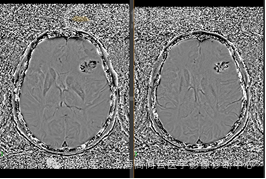

SWI

左额叶见不规则团块状异常信号影,边界欠清,大部分 T1WI 呈稍低、低信号,T2WI 及 T2 FLAIR 呈等稍高信号,内见点片状低信号,DWI 呈高信号,相应区域 ADC 呈稍低信号,ADC 值约 0.793 ×10-3 mm2/s,最大横截面大小约 44 mm×55 mm,病灶后部 T1WI 呈低信号,T2WI 呈高低混杂信号,FLAIR 呈稍低等混杂信号,SWI 呈明显低信号,DWI 以低信号为主,病灶周围见大片水肿信号影环绕,邻近侧脑室明显受压,左额部中线结构略右偏,增强后病灶呈明显不均匀强化,内可见不规则无强化坏死区,强化区域灌注扫描 CBF 增高,MRS 显示局部 Cho 峰明显升高,NAA 峰明显升高,Cho/NAA 比值约 87.02,出现 Lip 峰及 LAC 峰。3D T1WI 增强显示左侧额叶病灶邻近脑膜增厚强化;另外右侧颞窝底部可见小条状强化灶。